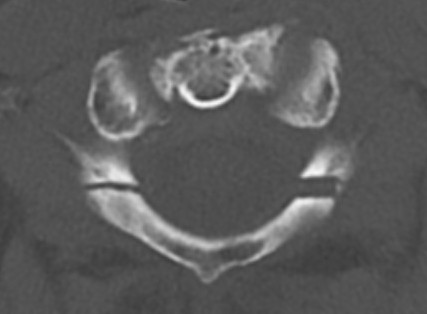

CT

Better defines displacement, ADI, LMD and bony avulsions of the transverse ligament

Avulsionlig avulsion

CT axial slices "Jefferson" (burst) fracture with bony avulsion (blue) of the transverse ligament

CT LMDCT Jefferson